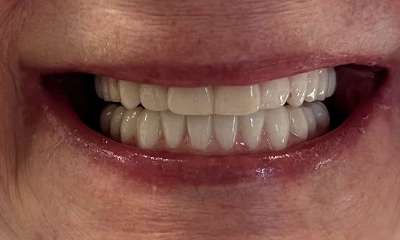

Crowned 10 teeth on the upper arch to transform the patient's smile and achieve their cosmetic goals!